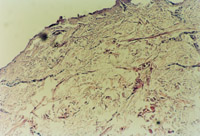

3-16 È¥µôÉÕÉË»µËÀƤ·ôÍâòµÄ¸¯Æ¤

3-17 È¡ÉÕÉËÆ¤·ô×éÖ¯¾ÙÐÐ×éÖ¯ÇÐÆ¬£¬£¬£¬ £¬ £¬£¬£¬£¬Õï¶ÏΪȫºñƤ»µËÀ£¬£¬£¬ £¬ £¬£¬£¬£¬²¿·ÖÖ¬·¾²ã×éÖ¯»µËÀ

3-18 ¶ÔÉÕÉËÆ¤·ô¾ÙÐиû×÷Ëɽ⣬£¬£¬ £¬ £¬£¬£¬£¬·óÓÃMEBO,½ÓÄÉ MEBTÁÆ·¨

3-19 ÉÕÉËµÄÆ¤·ô»µËÀ×éÖ¯×îÏÈÒº»¯£¬£¬£¬ £¬ £¬£¬£¬£¬¿ÉʵʱÕûÀí

3-20 »µËÀƤ·ô±»Òº»¯É¨³ý£¬£¬£¬ £¬ £¬£¬£¬£¬×é֯ѧ¼ì²éƤÏÂ×éÖ¯ÓÐÐÂÆ¤·ô×éÖ¯·ºÆð